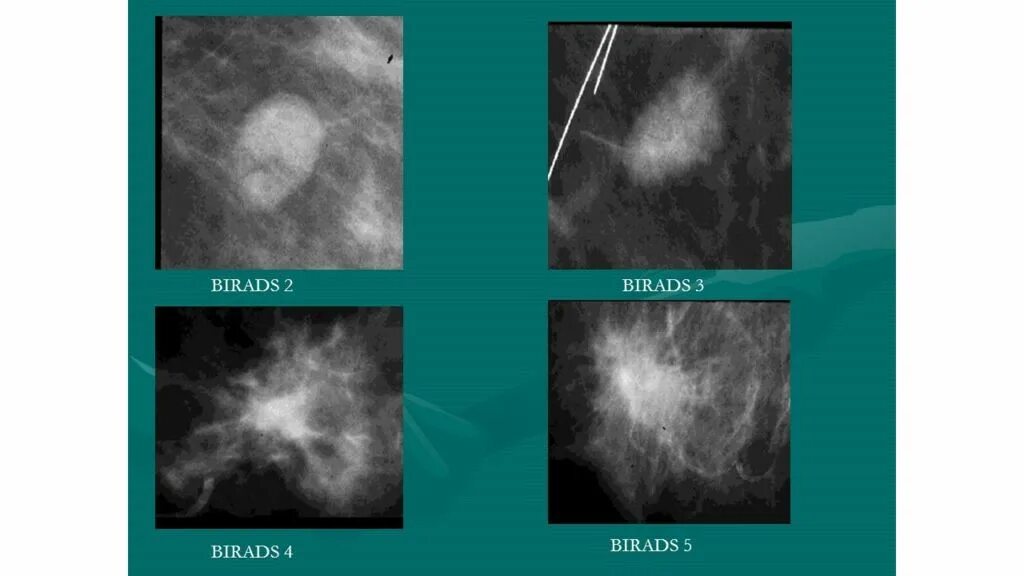

Что значит birads 3